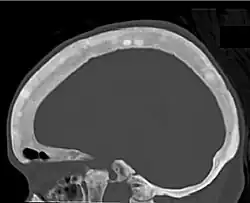

Ground glass density of the skull.[18] -

CT shows focal areas of osteosclerosis.[18] -

CT scan of the same case.[18]